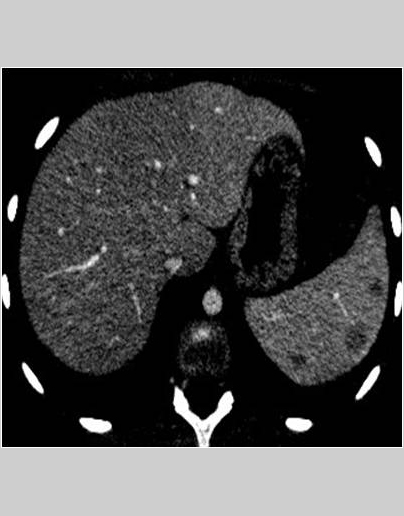

Se aprecian cuatro lesiones hipodensas en el bazo. En los cortes coronales se aprecia hipercaptación mucosa en las asas del yeyuno, adenopatías de tamaño patológico, aumento de la vascularización del meso y líquido libre en la fosa iliaca derecha.

• Se observan al menos cuatro lesiones focales esplénicas, hipodensas y mal definidas, con bazo de tamaño normal.